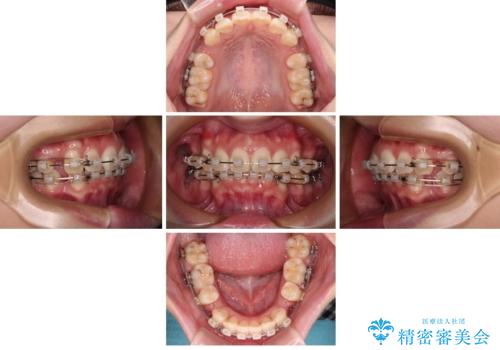

口元が出ているのを改善したい。 クリアブラケットによる抜歯矯正

- 前歯部のデコボコと口元が出ているのが気になるとのことで来院された患者様です。

口元の突出感の解消と、このままデコボコを解消するとさらに出っ歯傾向になってしまうことを考慮し、上下左右の小臼歯を抜歯しクリアブラケットにて矯正していくこととしました。

舌突出癖を改善するトレーニングを一生懸命やっていただいたおかげで2年以内に治療を終えることができました。